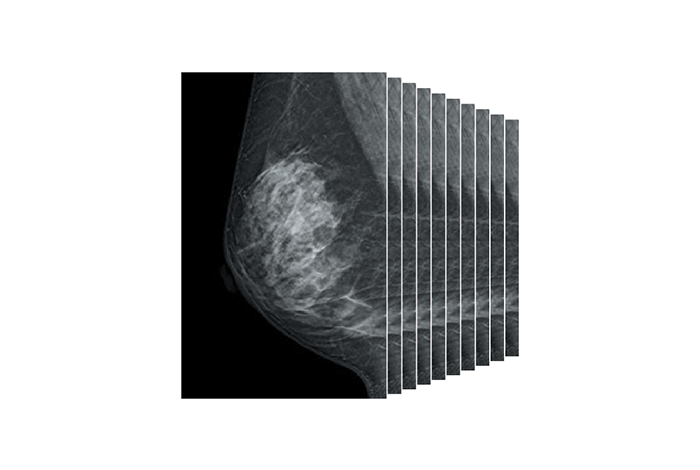

Digital Breast Tomosynthesis (DBT)

• Captures low-dose images at multiple angles, reconstructing high-resolution slices to improve lesion detection in dense breast tissue.

• Achieves superior diagnostic accuracy and reduced recall rates for false positives compared to standard digital mammography.